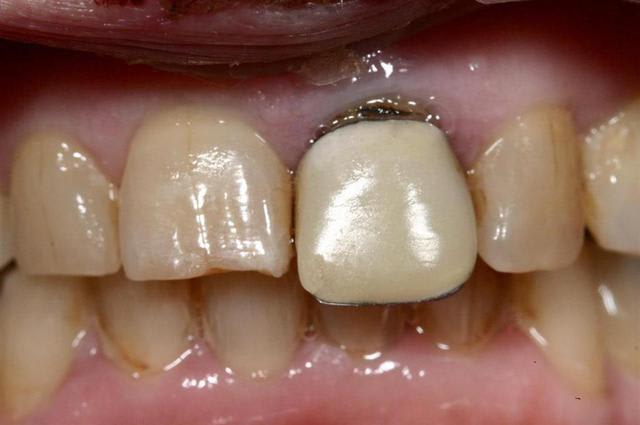

c'est tout simplement un faux moignon "droit" en titane idi

ils ont tous ce petit trou que j'utilise parfois pour l'enlever, lors des essais

Quel que soit le diamètre de 2,8 à 3,7 le col fait 4mm, cela simplifie la prothèse (peut être trop)

L'axe est effectivement un peu vestibulaire

photo d'un faux moignon droit